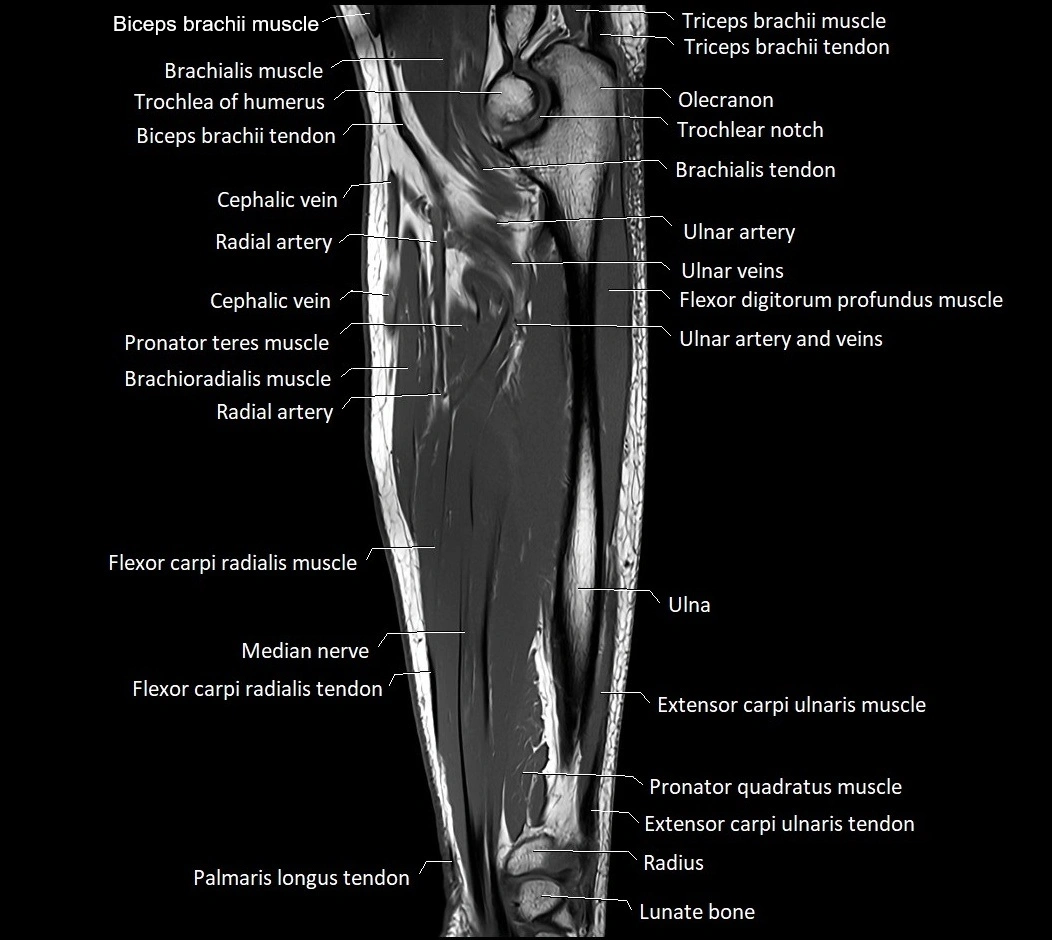

MRI images

image